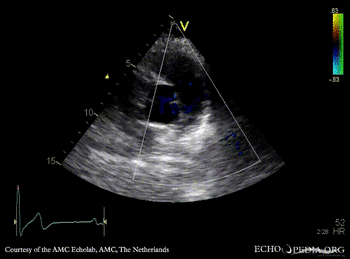

Severe pulmonary regurgitation

E00381.jpg

PSAX: Color Doppler, severe pulmonary regurgitation Continuous-wave signal of transpulmonary flow